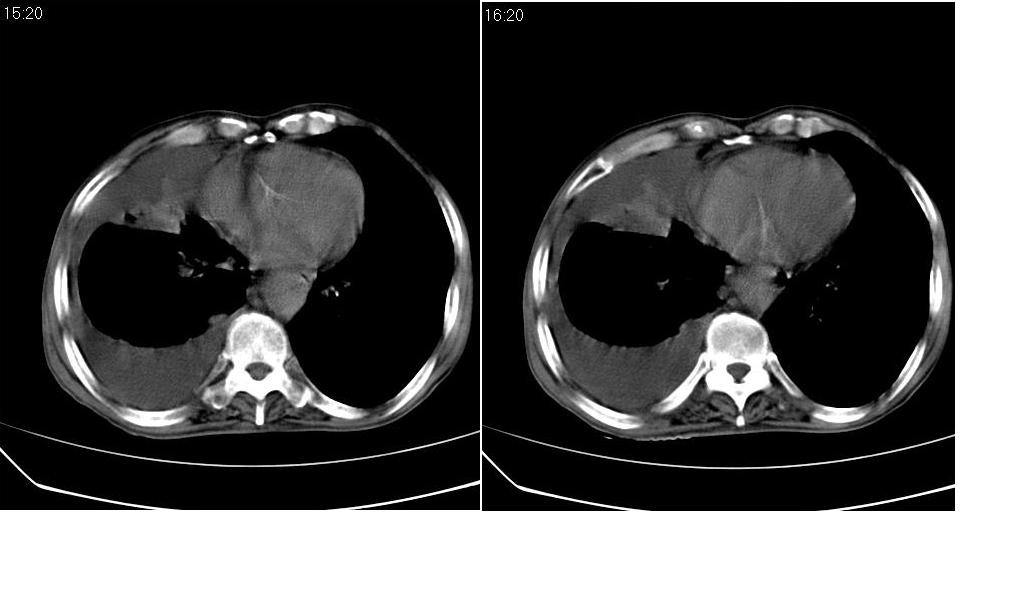

以下是引用zsl6918在2008-5-3 19:53:00的发言:[br]右肺中心型肺癌并纵隔淋巴结转移,胸膜转移,右肺癌性淋巴管炎。

以下是引用liuyue在2008-5-3 20:49:00的发言:[br]1.右侧中心型肺癌伴双肺转移瘤、纵隔淋巴结转移、右侧胸腔积液(侵及胸膜所致可能性大)。[br]2.右肺阻塞性肺炎,癌性淋巴管炎不除外。

以下是引用mzh123在2008-5-3 21:12:00的发言:[br]本人持有不同观点[br]1、右肺似有团块表现,但只有一个层面,所以本人认为还是以片为主,所以不能首先考虑肿瘤[br]2、右肺普遍成纤维化改变 并伴有片状炎症改变,和癌性淋巴管炎表现不同[br]3、所以本人认为是间质纤维化伴感染可能大 及胸腔积液